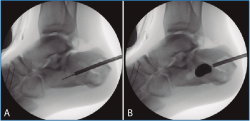

En los 4 casos con osteosíntesis percutánea, una vez levantado el fragmento, se realiza una fijación provisional con agujas de 1,8 mm (Figuras 4B y 4C), que podemos emplear, además, para manipular el fragmento y mejorar la corrección. A continuación, se procede a la inserción de los tornillos canulados de 3,5 mm de lateral a medial, solidarizando el fragmento lateral con el anteromedial (Figura 4D). Se debe combinar la visión artroscópica con una visión radiológica que nos confirme la posición y longitud adecuada de los tornillos.

Figura 4. A: control de escopia intraoperatoria (perfil) de la lesión reducida con ayuda de periostotomos; B: control de escopia intraoperatoria (perfil) tras insertar la primera aguja mientras se mantiene la reducción con un periostotomo; C: control de escopia intraoperatoria (axial de calcáneo) tras insertar la primera aguja mientras se mantiene la reducción con un periostotomo; D: control de escopia intraoperatoria (axial de calcáneo) tras colocación del primer tornillo de osteosíntesis.